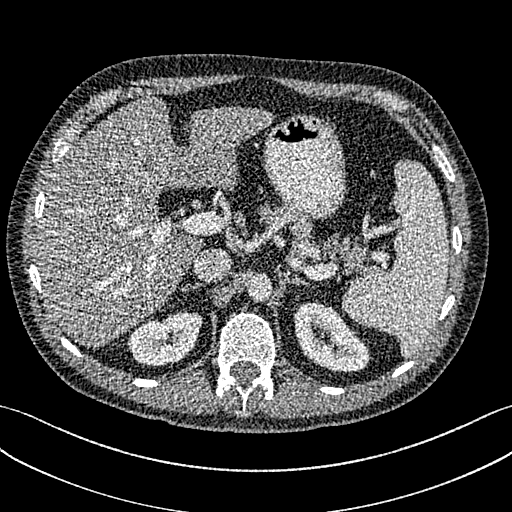

To demonstrate the effectiveness of the proposed network, we perform the qualitative comparisons over three representative abdominal images presented in Figs. 3, 5 and 7. For better evaluations of the image quality with different denoising models, zoomed regions-of-interest (ROIs) are marked by red rectangles and shown in Figs. 4, 6 and 8 respectively. Note that all results from different denoising models focus on two aspects: content restoration and noise-reduction. All CT images in axial view are displayed in the angiography window [-160, 240]HU.

The real NDCT images and corresponding LDCT images are presented in Figs. 3a and 3b. As observed, there are distinctions between ground truth (NDCT) images and LDCT images. Figs. 3a and 7a show the lesions/metastasis. Fig. 5a presents focal fatty sparing/focal fat. In Figs. 4a, 6a and 8a, these lesions can be clearly observed in NDCT images; in contrast, from Figs. 4b, 6b, and 8b, it can be seen that the original LDCT image is noisy, and lacks structural features for task-based clinical diagnosis. All adopted denoising models suppress noise to some extent.